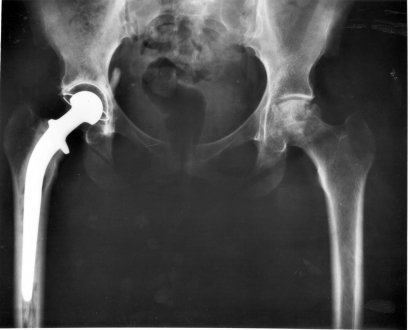

Wanneer een hond zwakker begint te worden – of zelfs verlamd raakt – in zijn achterpoten, zijn er drie belangrijke oorzaken: neurologisch, orthopedisch of symptomatisch. Wanneer de oorzaken neurologisch zijn treedt er iets op dat paraparese of acute paraplegie wordt genoemd.

Deze meest voorkomende oorzaak van deze vorm van verlamming (die begint met zwakte van het achterlijf) is meestal een degeneratieve wervelschijfziekte. Die komt zeer vaak voor bij honden maar is zeer zeldzaam bij katten.

Deze aandoening staat bekend als een Hansen type I hernia. Er is ook een Hansen type II dat een meer chronische progressie kent, waardoor het minder agressief is.

Hoe langer je hond met een onbehandelde hernia rondloopt, hoe ernstiger de nasleep kan zijn. Maar als je dit op tijd opmerkt kan het probleem door middel van een operatie worden aangepakt.

Chirurgie bij Hansen I

Hoewel wij je niet kunnen adviseren of een operatie een goed idee is, kunnen wij je wel de nodige informatie verstrekken. Op die manier kun je een weloverwogen beslissing nemen. Allereerst is het belangrijk om te begrijpen dat niet alle operaties helpen.

Er is echter een relatief hoog slagingspercentage wanneer de ziekte op tijd wordt gediagnosticeerd.

Het hangt allemaal af van wat de neuroloog zegt. De operatie kan meestal worden vermeden als het dier ondanks een hernia nog steeds kan lopen. Meestal ook als de chirurg zegt dat de schijf alleen maar uitsteekt.

In dat geval zal je hond een zes weken durend behandelplan met een strikte rustperiode moeten doorlopen. Daarnaast zal hij een supplement met corticoïden en een maagbeschermer moeten innemen.

Mocht je besluiten de operatie te laten doen, dan moet je weten dat het dier een paar weken totale rust nodig heeft. De kans op het terugdraaien van de zwakte van het achterlijf is dan erg groot.